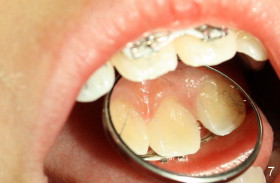

Eight-year-two-month girl has diastema between the maxillary central incisors.  It appears that the upper labial frenum (Fig.3 arrowheads, mirror view) bisects the interdental papilla (Fig.5).  Frenectomy is planned before orthodontic closure of the diastema.  Fig.4 is pre-op X-ray. Five months later, the diastema is closed.  The frenum appears to recede upward (Fig.6).  The bisected papilla seems to fuse (Fig.6,7).  Although the diastema has tendency to relapse when power chains are not used, fixed lingual retainer is planned to prevent the relapse when brackets are to be removed.  It appears that frenectomy is not so highly necessary for this purpose.